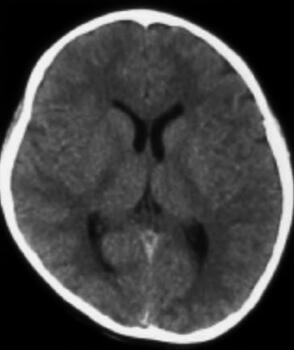

辅助检查:血常规(2010年10月21日):白细胞10.86×109/L,中性粒细胞0.83,血红蛋白129g/L,血小板301×109/L。颅脑CT平扫(2010年10月25日,图2):脑室系统饱满,双侧脑室后角室管膜下血管影显著,余颅脑平扫未见异常。超声(小器官)(2010年8月3日)检查结果:右侧髂腰肌内、髂外动静脉周围及腹股沟区皮下大片蜂窝状无回声区,考虑血管瘤。

图2 第二次颅脑CT检查(2010年10月25日):未见明显脑室及蛛网膜下腔出血